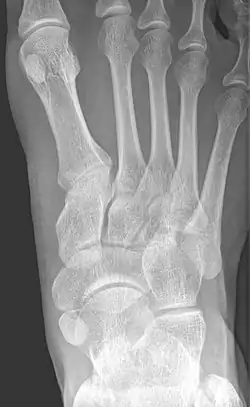

Accessory navicular bone

X-ray of the foot showing an accessory navicular bone

An accessory navicular bone is an accessory bone of the foot that occasionally develops abnormally in front of the ankle towards the inside of the foot. This bone may be present in approximately 2-21% of the general population and is usually asymptomatic.[1][2][3] When it is symptomatic, surgery may be necessary.